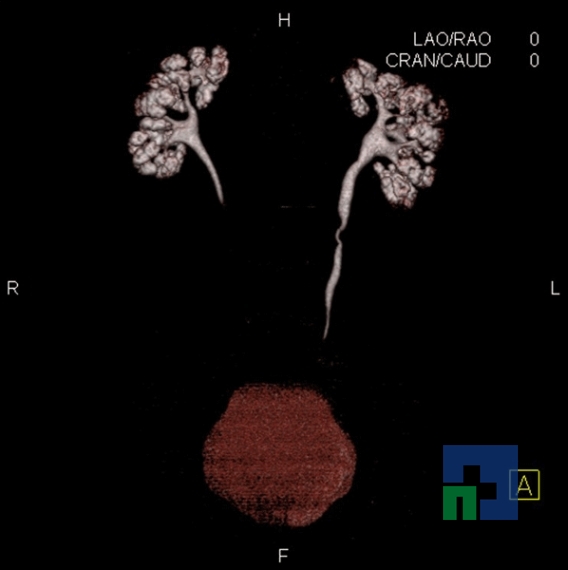

Examinare de rutină cerebrală, nativ și cu substanță de contrast (SDC) pentru diagnosticul:

- Accidentelor vasculare cerebrale ischemice sau hemoragice

- Tumorilor cerebrale